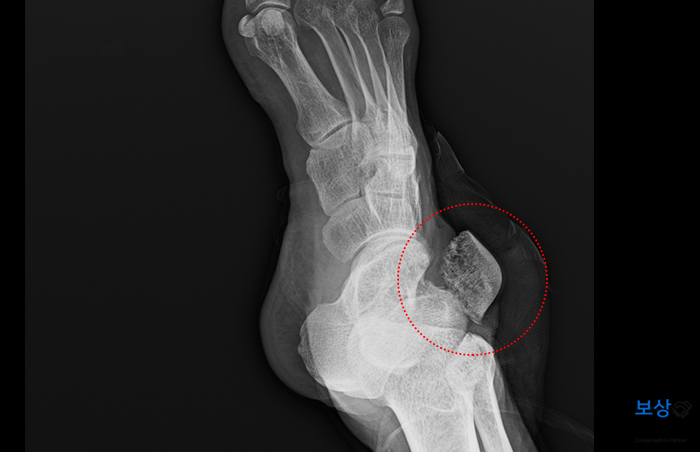

병 명 : 우측 족관절 거골 개방성 골절 (S9211) 우측 족관절 전거비인대, 종비인대, 삼각인대 파열 (S932) 우측 족관절 거골 탈구 (S9338) 진단명은 거골의 개방성 골절이었는데요. 거골은 발목 바로 아래 위치한 뼈이며 하중을 직접적으로 지지하는 역할을 합니다.

그리고 개방성 골절이란 뼈가 살 밖으로 드러난 형태를 말하는데요. 사고 당시 환부의 상태가 매우 좋지 않았음을 알 수 있습니다. 수술 전문 병원에서 급하게 골 정복술 및 금속 나사 고정술을 시행하여 골절된 뼈를 단단히 고정하였는데요.